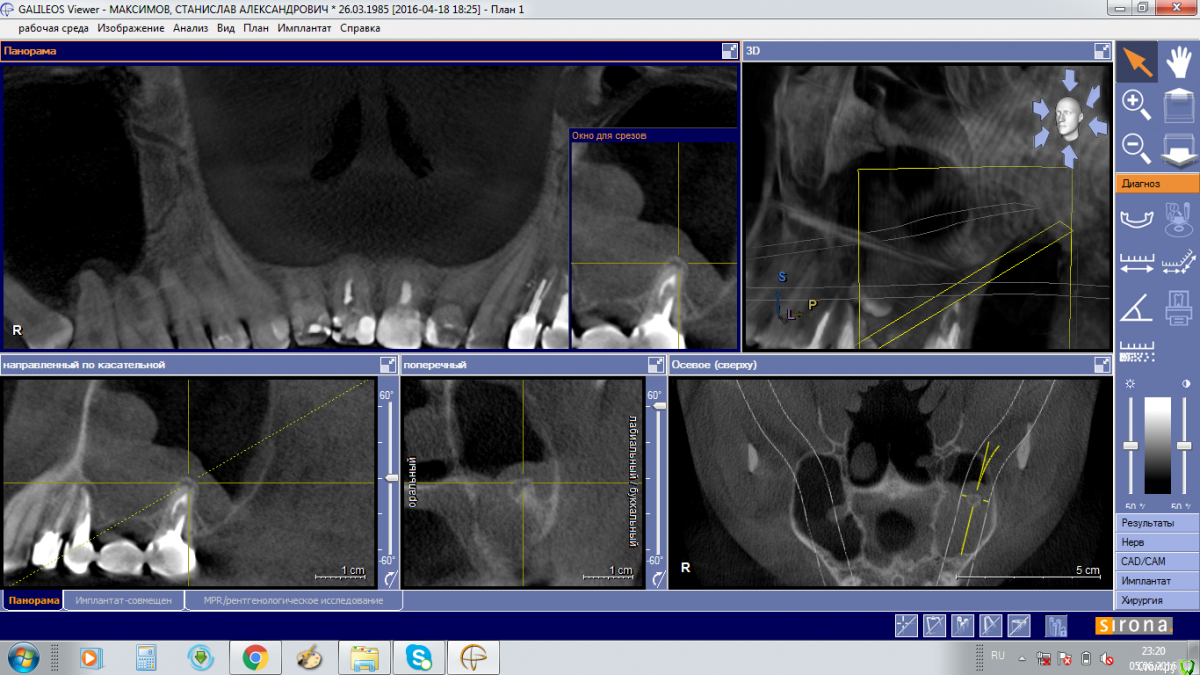

Stanis777 Опубликовано 6 июня, 2016 Поделиться Опубликовано 6 июня, 2016 Здравствуйте!Два месяца назад переболел левосторонним гайморитом, температура была до 39, 3 раза делали проколы. ЛОР выразил мнение о связи с зубами. Через 3 дня после пролечивания сделали КЛКТ, по результатам которого ЛОР сказал что в зубах 5 и 7 воспаление и отправил к стоматологу-хирургу. Стоматолог-хирург осмотрев меня и изучив КЛКТ сказал что в пазухе киста, которую нужно удалять эндоскопически и прямой связи с зубами не видит.Сейчас каких-то явных симптомов, кроме ощущения как бы небольшой припухлости левой щеки нет. В прикреплении фото с КЛКТ. Подскажите исходя из фото что нужно делать? Лечить-удалять зубы или киста не связана с ними? И в какое мед.учреждение в Москве лучше обратиться для лечения, желательно по ОМС. Ссылка на комментарий

Bier Опубликовано 6 июня, 2016 Поделиться Опубликовано 6 июня, 2016 проблемы в пазухе одонтогенные. (т.е. от зубов) Ссылка на комментарий

Doctor Vlad Опубликовано 8 июня, 2016 Поделиться Опубликовано 8 июня, 2016 5ка еще одно лечение не переживет Ссылка на комментарий

Bier Опубликовано 8 июня, 2016 Поделиться Опубликовано 8 июня, 2016 перелечить проблемно, скорее всего удаление. Ссылка на комментарий